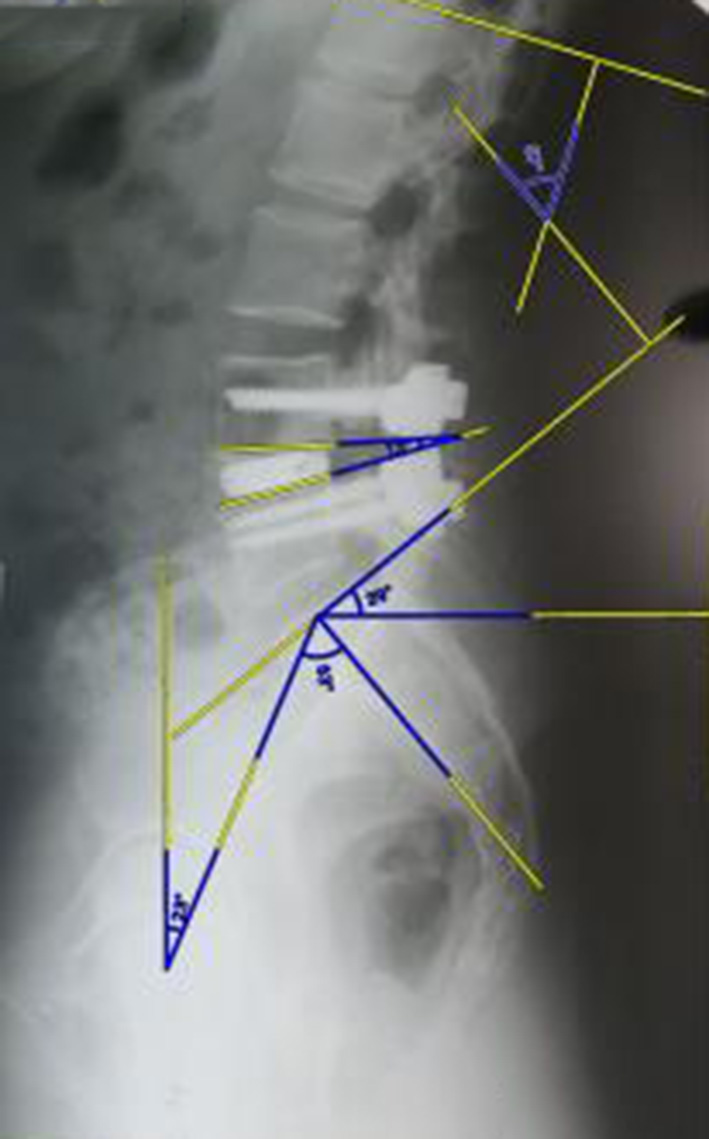

The clinical study involved 21 patients (15 women and 6 men), aged 32 to 68 years (median age – 56 (50; 65) years), divided into three groups: study group (n=4), where the author's technique of MIPIVS was applied (patent application No. a202302383 of 18.05.2023) (Fig. 3); comparison group (n=10), where the standard MIPIVS technique was used (Fig. 4); control group (n=7), where other interbody fusion techniques were employed (Fig. 5) .

Fig. 3. Radiographic control before and after surgery using the minimally invasive posterior interbody vertebral stabilization technique with titanium distraction cages